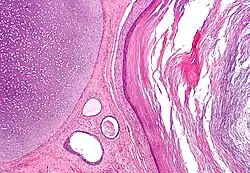

In the human embryo, after about three days, the zygote forms a solid mass of cells by mitotic division, called a morula. This then changes to a blastocyst, consisting of an outer layer called a trophoblast, and an inner cell mass called the embryoblast. Filled with uterine fluid, the blastocyst breaks out of the zona pellucida and undergoes implantation. The inner cell mass initially has two layers: the hypoblast and epiblast. At the end of the second week, a primitive streak appears. The epiblast in this region moves towards the primitive streak, dives down into it, and forms a new layer, called the endoderm, pushing the hypoblast out of the way (this goes on to form the amnion.) The epiblast keeps moving and forms a second layer, the mesoderm. The top layer is now called the ectoderm.[6]